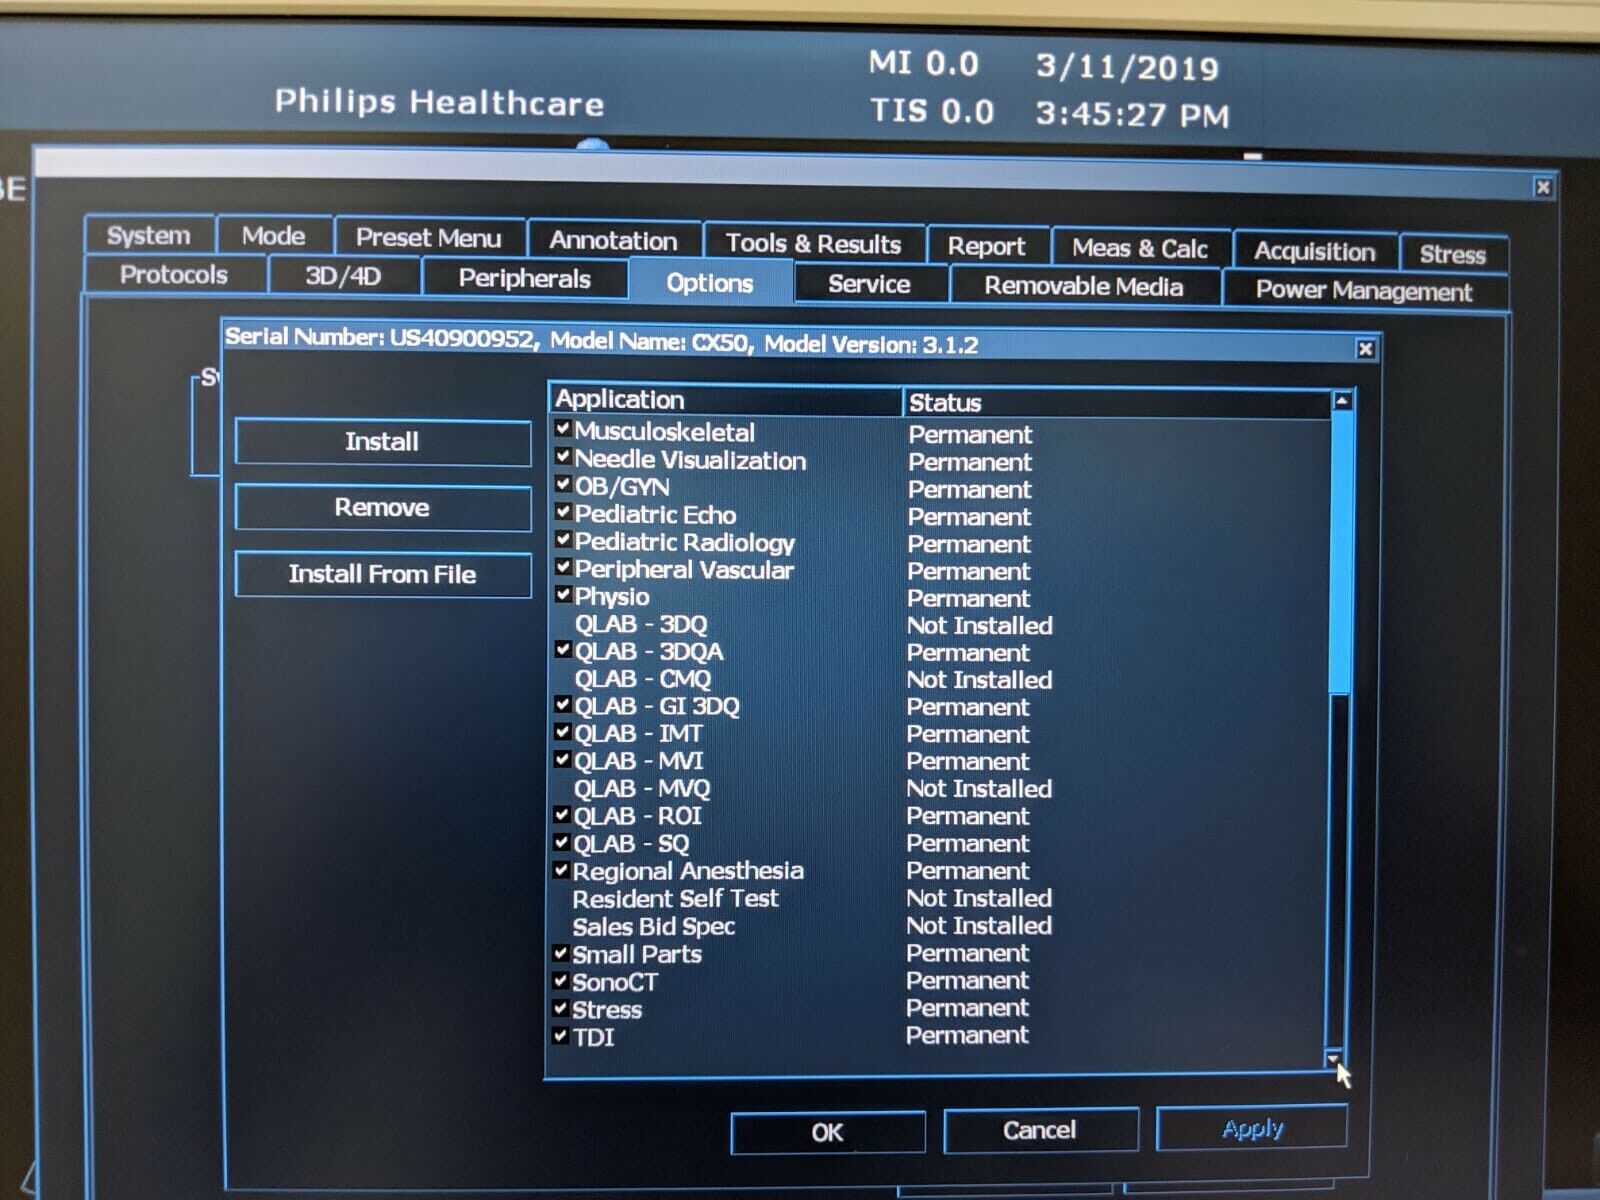

The Philips CX50 2013 Rev 4 Portable Ultrasound System with three probes is a high-performance imaging solution designed for flexibility across a range of clinical applications. This compact, portable ultrasound machine delivers premium imaging quality, making it ideal for point-of-care, cardiology, vascular, and emergency medicine. Equipped with Philips’ advanced imaging technologies like PureWave crystal technology, the CX50 provides exceptional resolution and detail, even in difficult-to-image patients.

The three included probes offer versatility, allowing clinicians to perform various exams, from cardiac and vascular to abdominal and superficial imaging. Its portability and lightweight design make it easy to transport between departments or use in field settings, without compromising on diagnostic accuracy. The CX50’s intuitive interface and customizable presets streamline workflows, making it user-friendly for fast-paced environments. This system is an excellent choice for healthcare providers needing a portable ultrasound solution that offers advanced imaging capabilities and multi-specialty support.